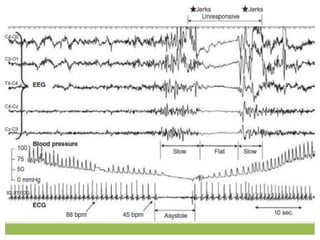

EEG changes in syncopal subjects

(2 patterns)

 “Slow-flat-slow” pattern

 normal background activity is replaced with high-amplitude slow delta.

This is followed by sudden flattening of the EEG—a cessation or

attenuation of cortical activity—followed by the return of slow waves, and

then normal activity.

 “Slow pattern,”

 is characterized by increasing and decreasing slow wave activity only

 EEG flattening in the slow-flat-slow pattern denotes severe cerebral

hypoperfusion.

 Despite the presence of myoclonic movements and other motor activity

during some syncopal events, EEG seizure discharges are not detected.

 Convulsive syncope is a term used for any type of syncope

manifesting with convulsive movements.